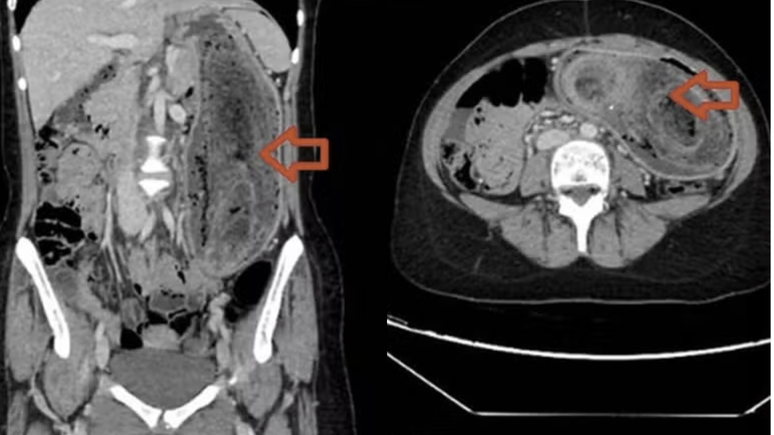

Na avaliação física, os médicos perceberam que o abdômen estava distendido, doloroso e com uma massa endurecida perceptível ao toque. Exames de imagem confirmaram a suspeita: havia um aglomerado de cabelo tão grande que ocupava completamente o estômago e chegava até o duodeno, configurando um quadro típico da "síndrome de Rapunzel".

"Devido ao tamanho, não foi possível remover o material por endoscopia. Foi necessário realizar uma cirurgia aberta sob anestesia geral", relataram os autores do estudo. A operação durou cerca de três horas, e os cirurgiões conseguiram retirar a bola de cabelo intacta.